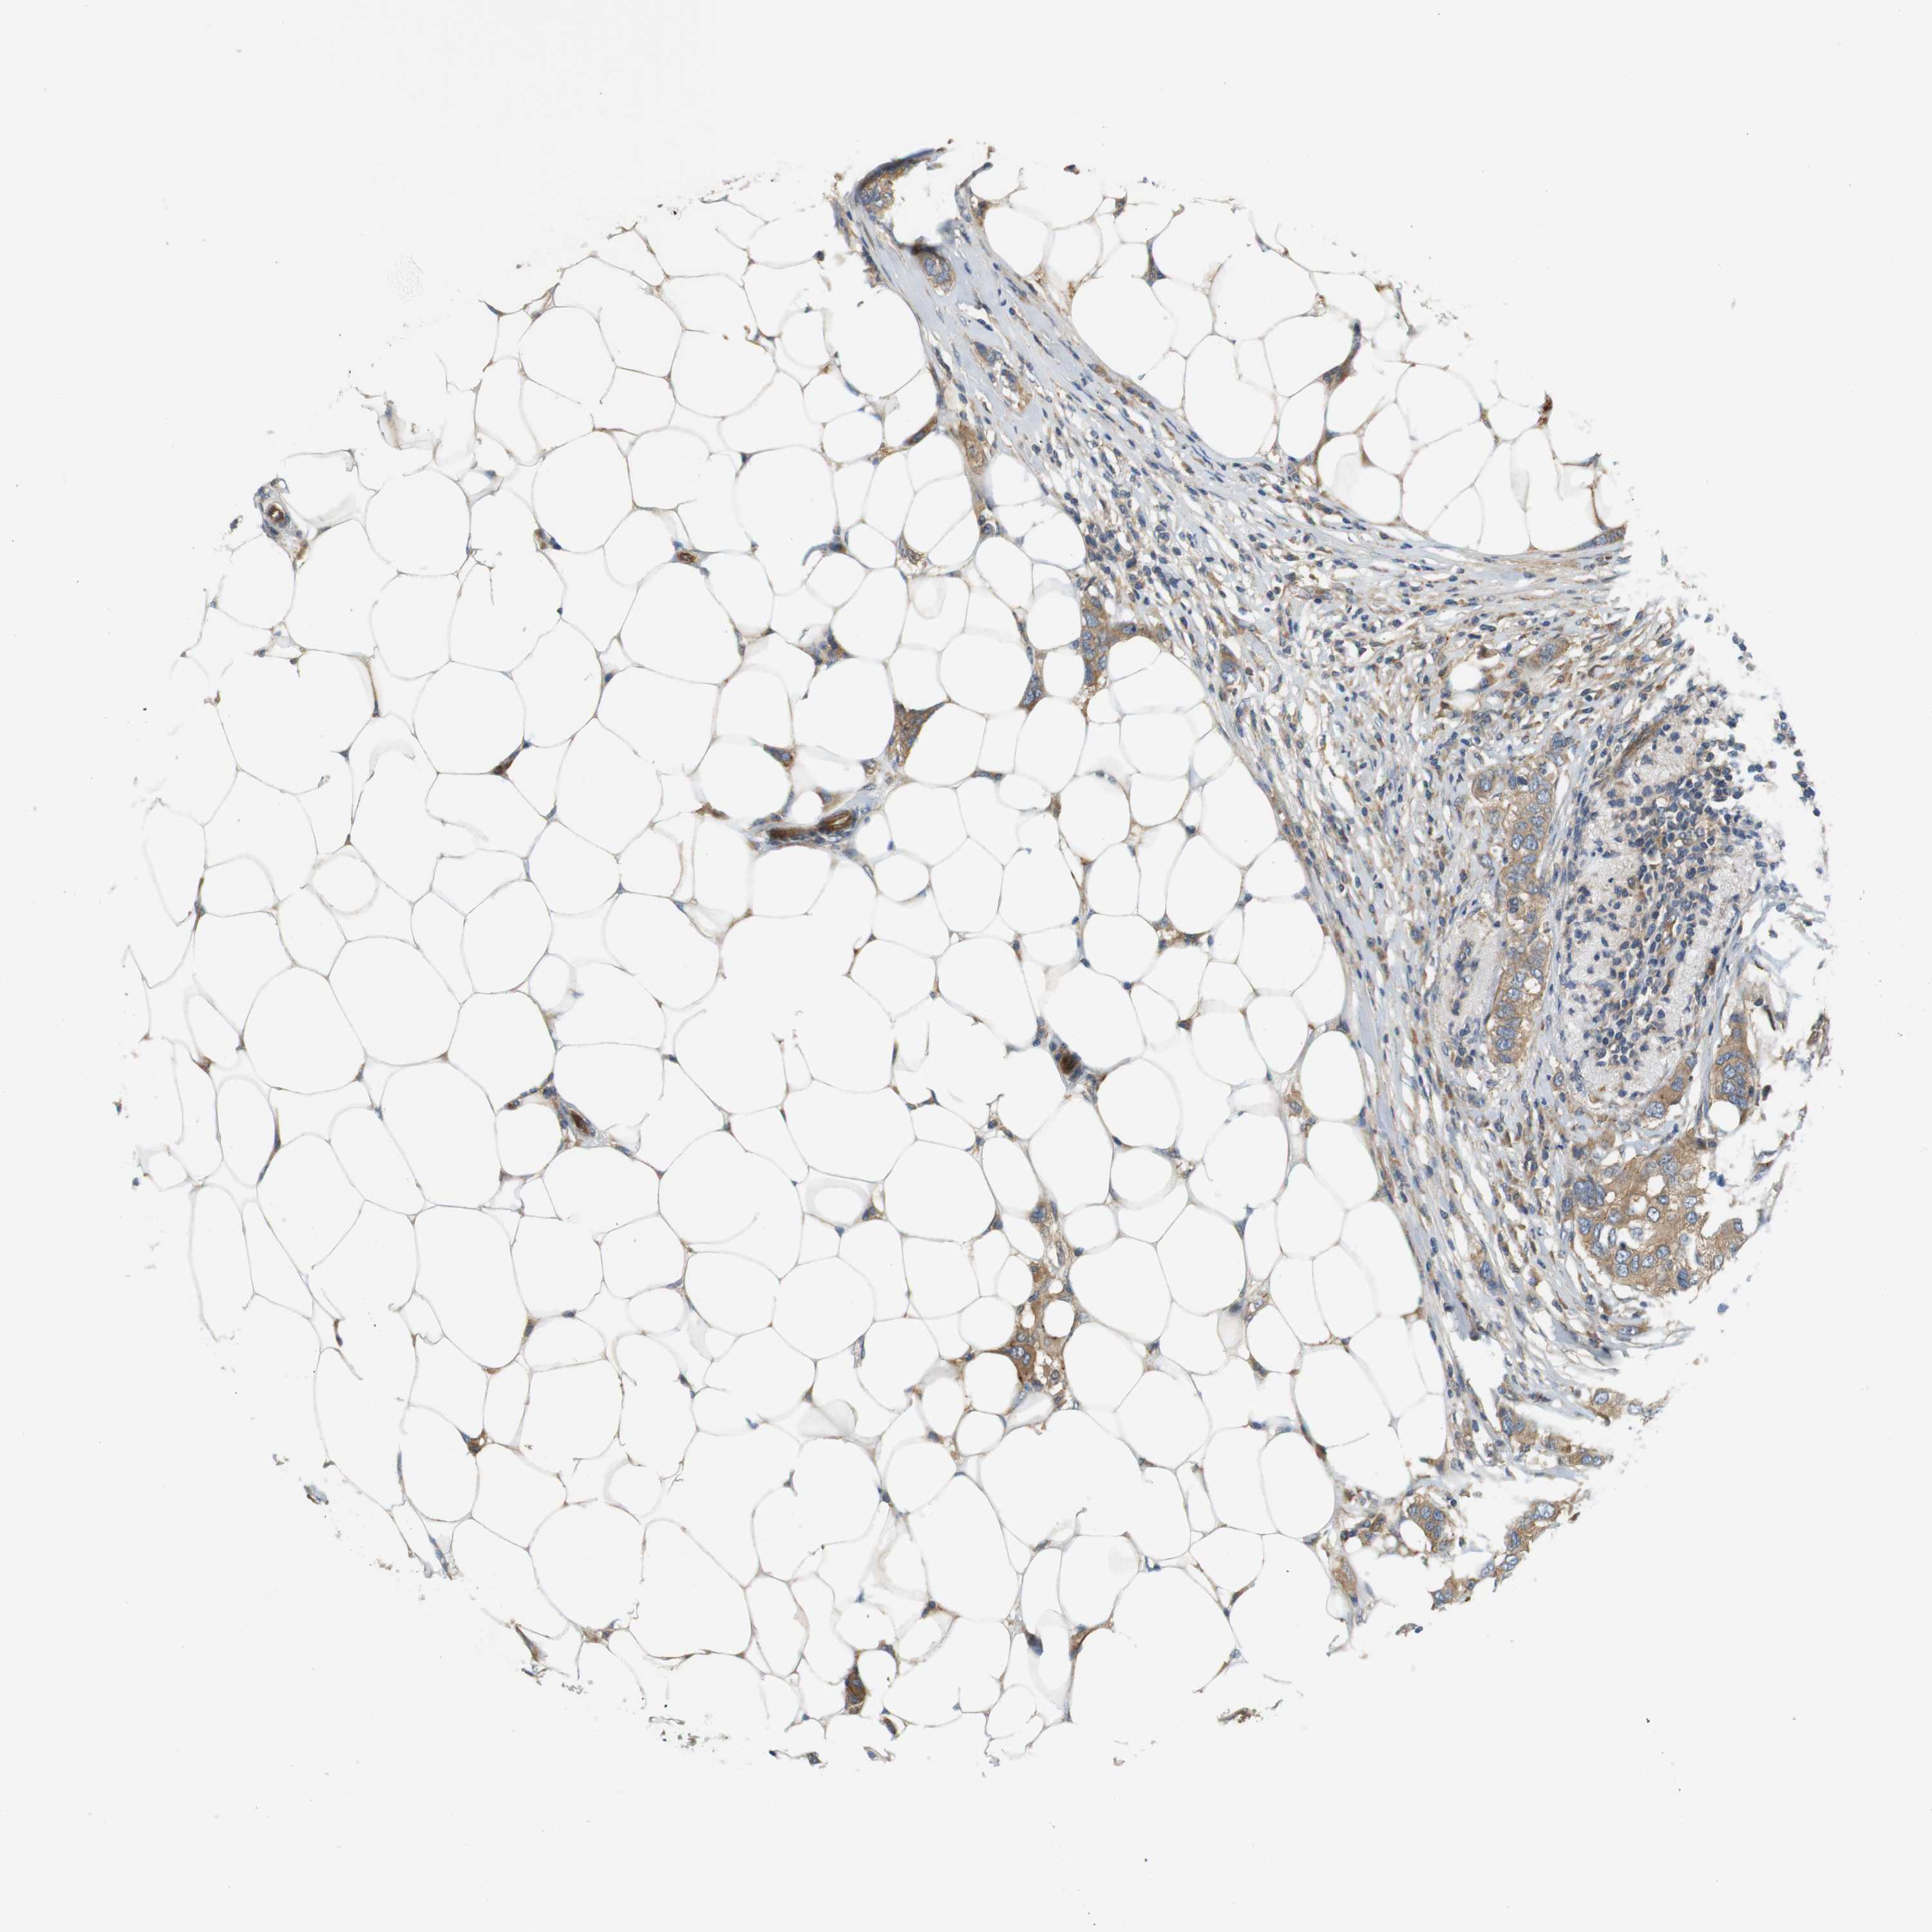

CANCER BREAST CANCER Show tissue menu

BRCA TCGA BRCA VALIDATION PROTEIN EXPRESSION